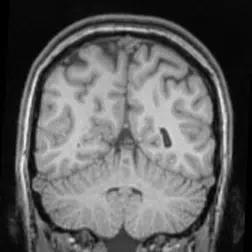

“What microwave radiation does in most simplistic terms is similar to what happens to food in microwaves, essentially cooking the brain,” said Dr. Keith Black, chairman of neurology and world class brain surgeon at Cedars-Sinai Medical Center in Los Angeles. “So in addition to leading to a development of cancer and tumors, there could be a whole host of other effects like cognitive memory function, since the memory temporal lobes are where we hold our cell phones.” Dr Black recommends using ear buds or texting to keep the cell phone away from the head.